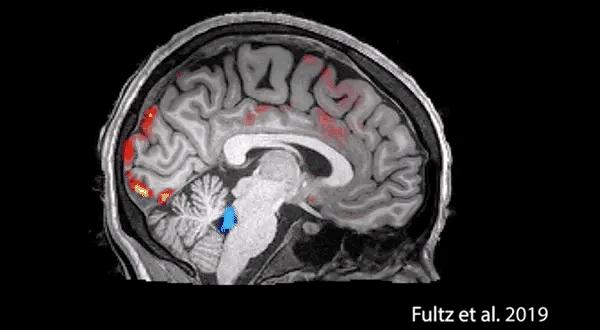

大脑主要掌管自控力和决策力的重要部位——前额皮质,前额皮质的自控力功能分成三个区域。

前额皮质的左边区域负责“我要做”的力量 ,它能帮你处理枯燥、困难或充满压力的工作,负责统筹协*情调**绪冲动与认知、控制人在面对挑战时的行为,以及帮助人们根据情况调整行为策略。

右边的区域则控制“我不要”的力量 ,它能克制你的一时冲动,掌管个体的注意力,认知力,以及遵守规则、控制冲动、推理和决策的能力。

第三个区域位于前额皮质中间靠下的位置。它会记录你的目标和欲望,决定你“想要什么”, 负责与“奖赏”有关的行为决策。

这个区域的细胞活动越剧烈,你采取行动和拒绝诱惑的能力就越强。

我们的大脑可以分为上层大脑和下层大脑,上层大脑由大脑皮层及其各个部分构成,尤其是额头后面的部分,包括前额叶皮层。

上层大脑进化程度更高,可以以更加全面的视角看待世界。在这里能发生更为全面的心理过程,比如思考、想象和规划。

我们希望孩子产生的很多品质都在此产生:明智的决策、对身体和情绪的控制、自我认识、共情、道德。

如果上层大脑发挥正常作用,孩子就会表现得成熟健康,能够理智地处理突发问题。

所以想要提升孩子的自控能力,就必须要加强对于大脑皮质前额叶区域的锻炼,通过参与脑电生物反馈训练,可以更为精确的训练大脑不同区域,让前额叶得到充分锻炼和发育。